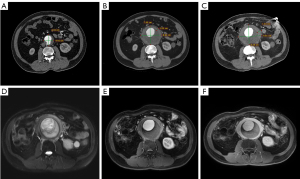

De novo PAF post-EVAR

Additionally, eight patients developed PAF after EVAR (Figure 3). An 80-year-old male patient’s first CTA scan in December 2018 suggested that the abdominal aorta was dilated, with a smooth aortic wall (as shown in Figure 3A). Two months after the EVAR procedure, PAF was not seen around the aortic wall (as shown in Figure 3B). However, 6 months after EVAR, PAF surrounded the aortic wall (as shown in Figure 3C).